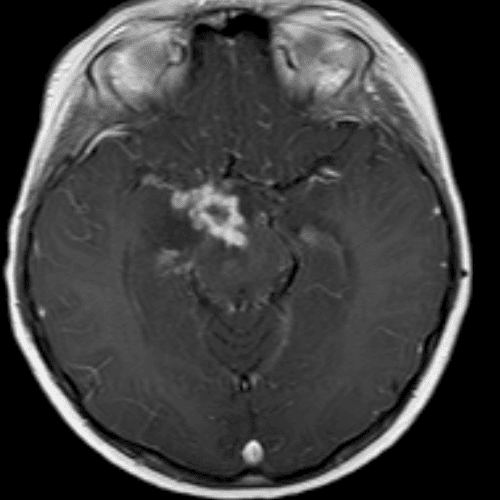

๋‹น์ง ์‹œ ํ”ํžˆ ๋ณผ ์ˆ˜ ์žˆ๋Š” ์‚ฌ๋ก€์˜ ์ „ํ˜•์ ์ธ ์˜ˆ๋ฅผ ํฌํ•จํ•ฉ๋‹ˆ๋‹ค.

39 ์‚ฌ๋ก€